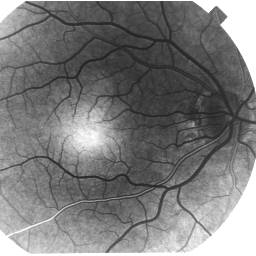

The fluorescein angiography may be given as a positive or negative transparency (see picture below). As most fluorescein angiographies encountered are on positive transparency, all the following interpretations are based on the apparance on positive tranparency.

Positive fluorescein angiography